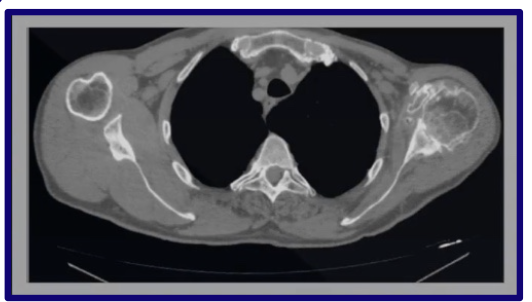

What is Computed Tomography (CT)?

An x-ray technology that creates very high-resolution thin slices of axial anatomy

How can CT images be displayed?

In different planes or reconstructions

How are radiodensities of tissues represented on CT?

By shades of gray

How does air appear on CT?

Air → Black

How does fat appear on CT?

Fat → Gray-Black

How does water appear on CT?

Water → Gray

How does bone appear on CT?

Bone → White

How is the CT image displayed?

As though the patient is supine and you are looking through the feet in axial view

What is windowing in CT?

A contrast enhancement technique that lets you visualize groups of radiodensities one at a time

Humans see 32 shades of gray, computers see thousands

CT scan can differentiate a 1% change in radiodensity, but it cannot be put all in one image, so it uses “windows” to visualize groups of radiodensities one at a time

Why is windowing important in CT?

It gives CT high sensitivity by emphasizing different tissue density ranges

What are the common CT windows?

Bone window and soft tissue window

Will show the ranges of raiodensities based on chosen tissue window

What are common clinical indications for CT?

Life-threatening injury evaluation

Complex & subtle fractures

Loose bodies in a joint

Degenerative changes

Spinal stenosis

What are the major advantages of CT?

Fast image acquisition time

Images bone and soft tissue in one series

Can view large body regions

Best in emergencies

Excellent bone definition

Why is CT often preferred over MRI for cortical bone?

Better cortical bone definition

Less time-consuming ⏰

Less expensive 💰

Less claustrophobia

Metal implants are generally less of an issue

What is the major disadvantage of CT?

High radiation exposure